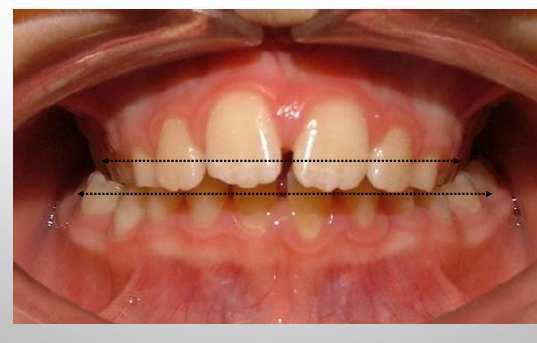

intraoral exam- vertical

-frontal (vertical) plane- use the frontal photos

-overbite

-open bite

-occlusal cants

overbite

-the amount of overlap of the mandibular anterior teeth by the maxillary anterior teeth measured perpendicular to the occlusal plane

-recorded in mm or percentage of lower incisor coverage (percentage preferred)

-coverage could be buccally

open bite

-present when there is no vertical overlap of the maxillary and mandibular anterior teeth or no contact between the maxillary and mandibular posterior teeth

-recorded as mm between incisal edges of maxillary and mandibular teeth

-can also record as negative overbite (i.e. -5mm overbite)

intraoral exam- transverse

-transverse plane- use the frontal and buccal photos

-posterior crossbites

-midline analysis: coincidence with each other, coincidence with face

midline assessments

1) maxillary midline to facial midline

2) intermaxillary midline

3) mandibular midline to facial midline

intermaxillary dental midline

-maxillary dental midline: a line drawn perpendicular to the maxillary occlusal plane through the proximal contacts of the central incisors

-mandibular dental midline: a line drawn perpendicular to the mandibular occlusal plane through the proximal contacts of the central incisors

-if deviation- must say what direction and by how much